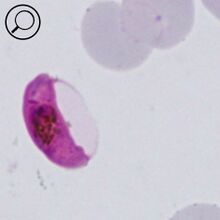

The gametocyte

The sexual replication in P.falciparum is very distinctive and may be the only form visible (particularly of after treatment).

- male and femaie gametocytes have the appearance of rods although these may be distorted

- The rod shapes may become curved by the red cell membrane to give the characteristic "banana" form”

- The residual membrane (empty of haemoglobin) is often seen as a "blister" to one or both sides of the parasite

- The single chromatin area is in the centre of the parasite, often has pigment overlying it

P.falciparum gametocytes